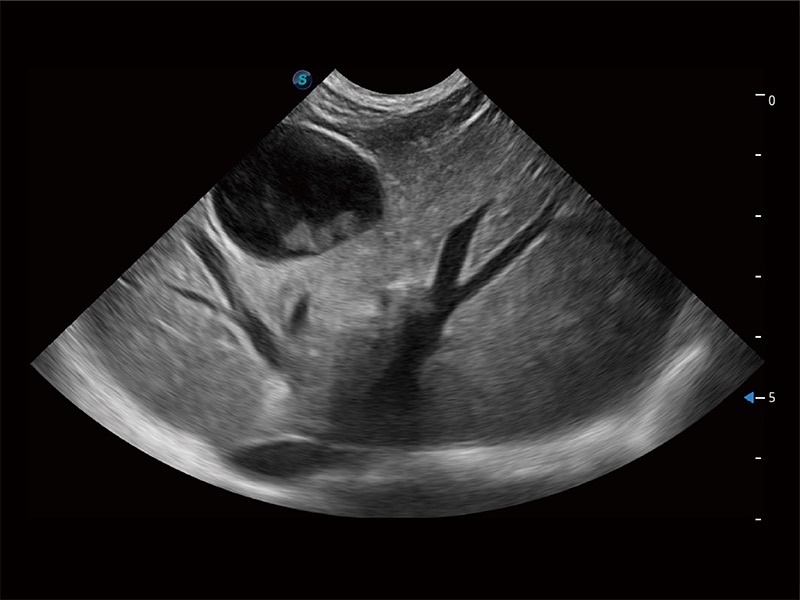

非线性融合造影成像充分利用谐波和基波信号,为难以观察的血流进行增强显像。可用于线阵、凸阵、微凸阵、相控阵探头。